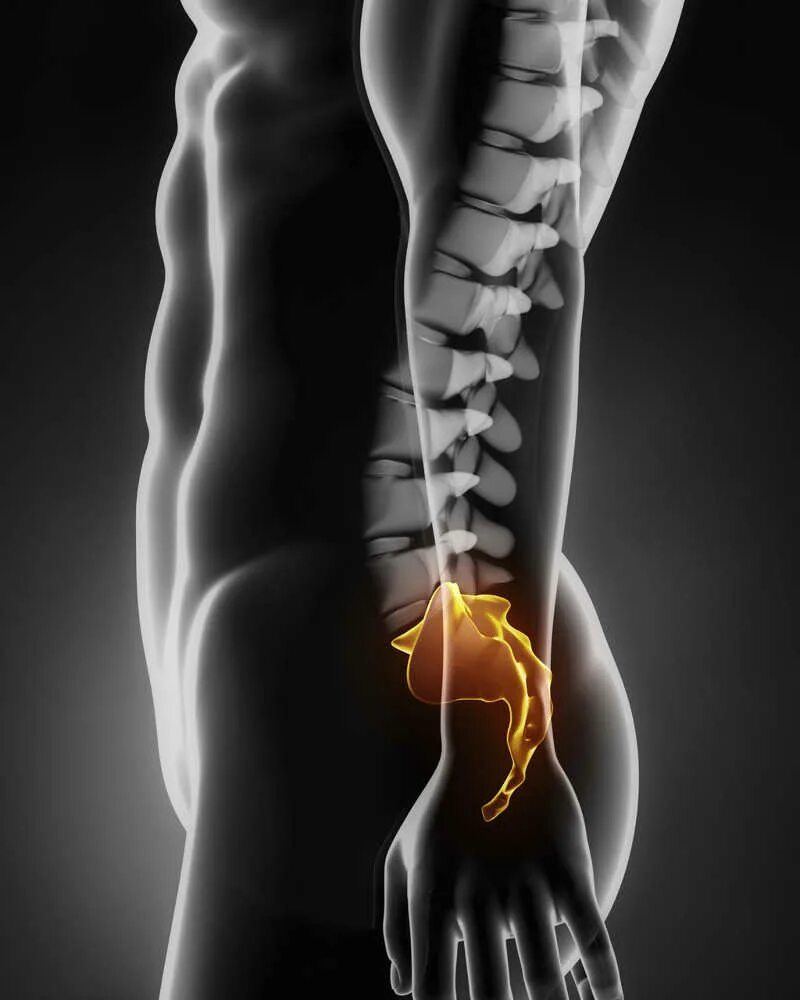

Пояснично крестцово копчиковый отдел